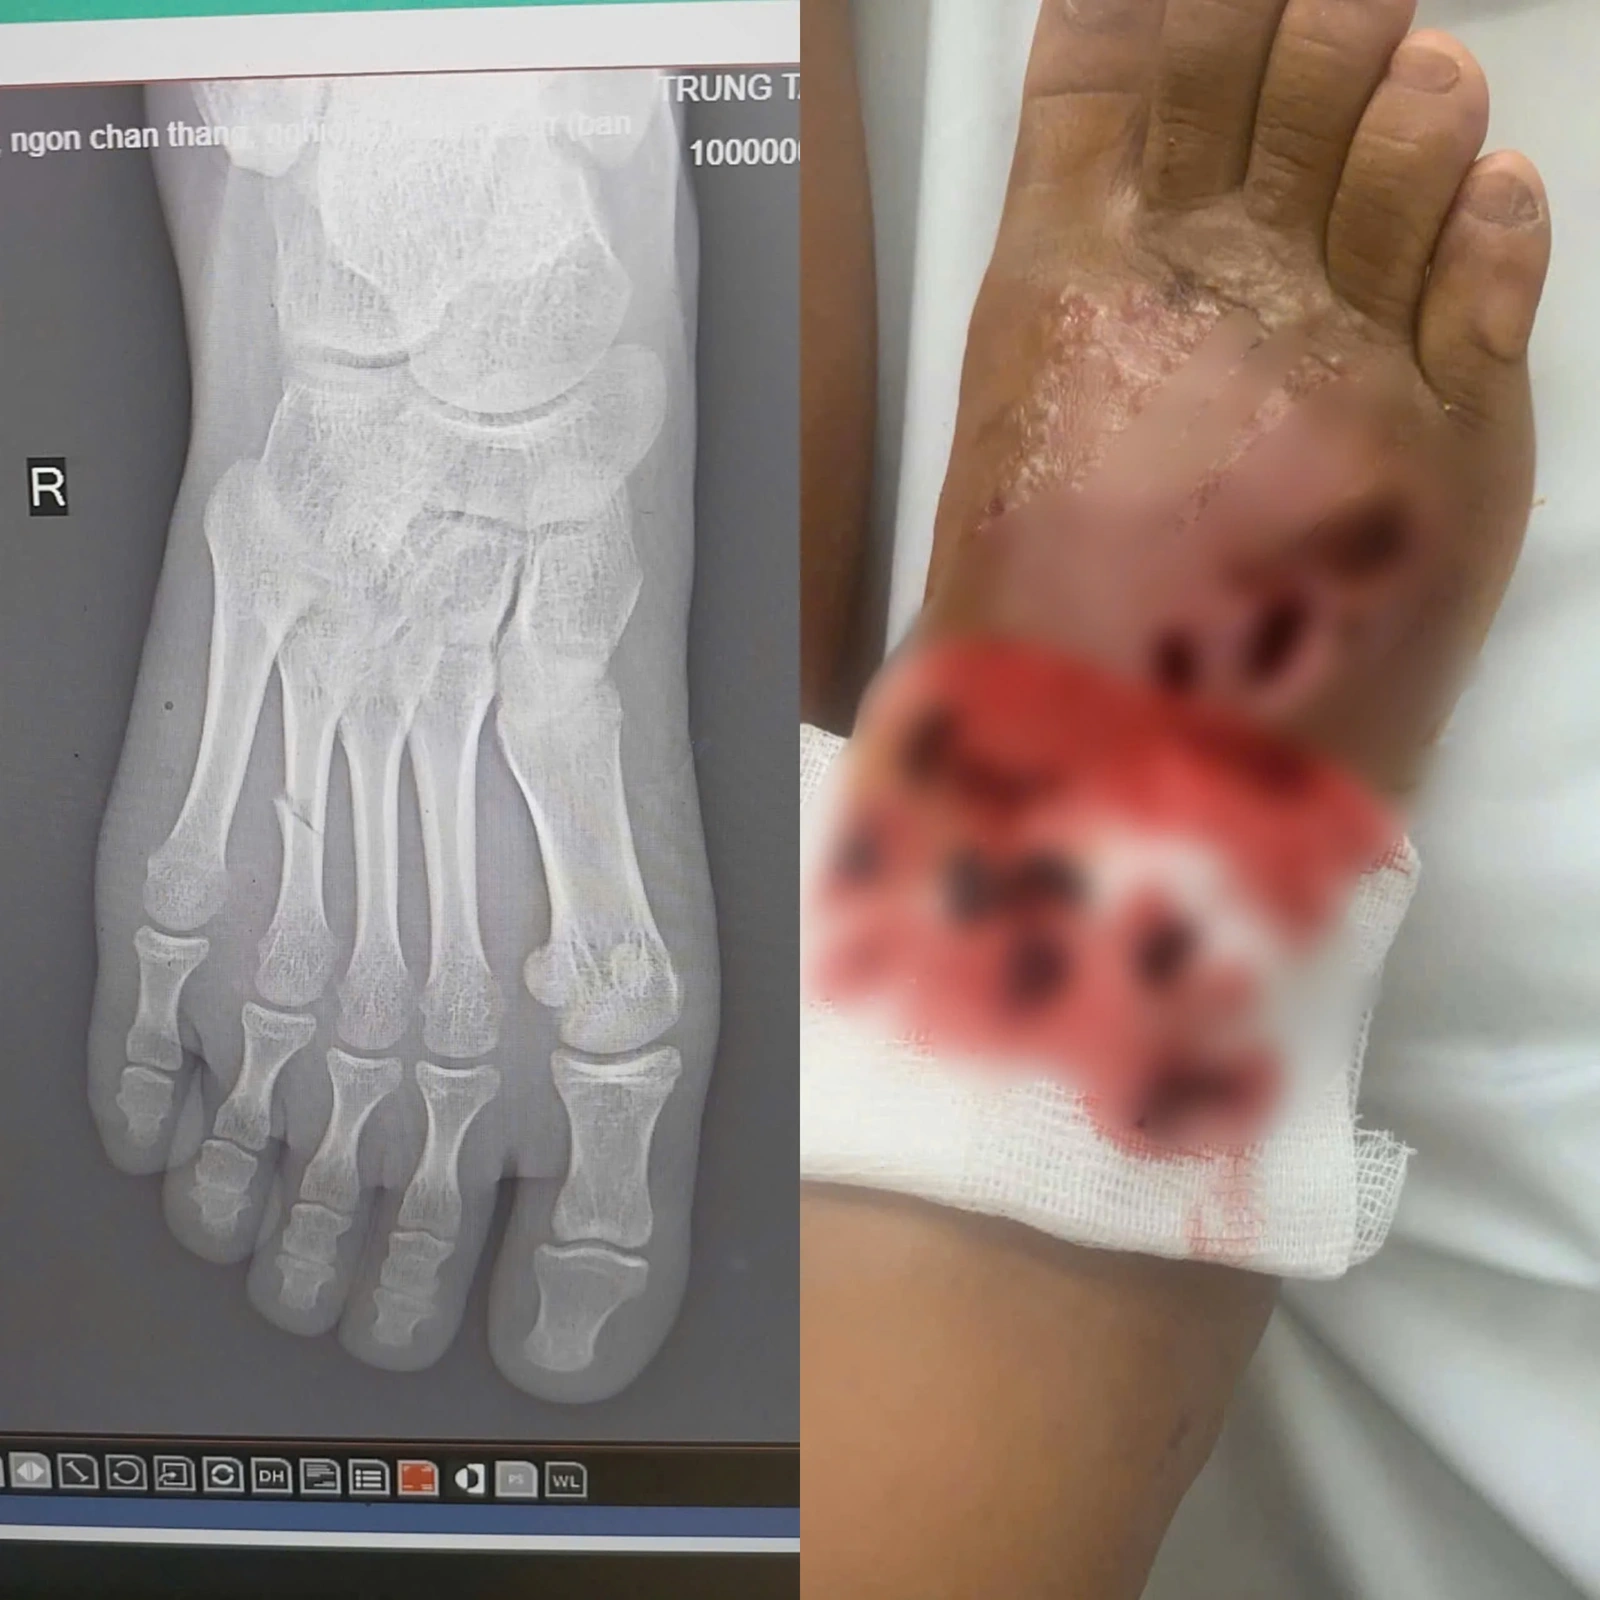

Tại đây, sau khi thăm khám lâm sàng và cận lâm sàng, kết quả trên phim chụp X-Quang cho thấy hình ảnh bị gãy xương đốt bàn chân/nhiễm trùng nặng bàn chân phải. Các bác sĩ đã loại bỏ ổ nhiễm trùng, điều trị kháng sinh liều cao cho bệnh nhi, bó bột hở vị trí loét. Sau 1 tuần điều trị, tình trạng nhiễm trùng được cải thiện, sức khỏe bệnh nhi ổn định.

Hình ảnh bàn chân bệnh nhân khi vào viện